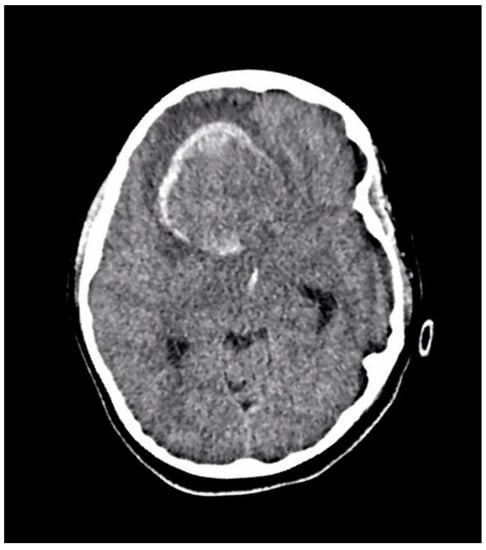

A ten-year-old boy with a history of autism and macrocephaly presented acutely with altered level of consciousness, emesis, left hemiparesis, left facial droop, and slurred speech in the context of a four-week history of intermittent headache and vomiting. Computed tomography (CT) scan demonstrated a large right frontal intraparenchymal hemorrhage and suspected underlying intra-axial mass with intraventricular hemorrhagic extension, mass effect, and midline shift (Figure 2). The patient underwent emergency craniotomy for debulking of the lesion and tissue diagnosis.

Figure 2.

An axial section of a non-enhanced head CT scan performed in the emergency department at the time of acute presentation. It reveals a large well-defined right frontal mass with solid and hemorrhagic components. There is surrounding edema and midline shift.